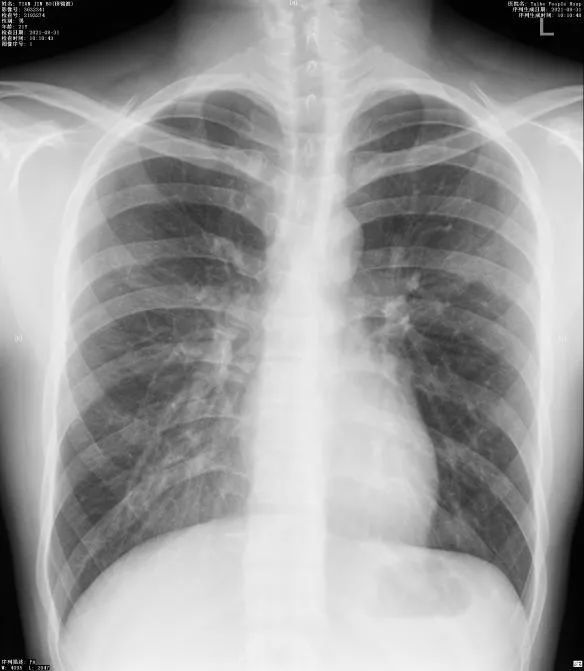

胸片--双肺纹理增多

两肺纹理增多,模糊代表什么意思